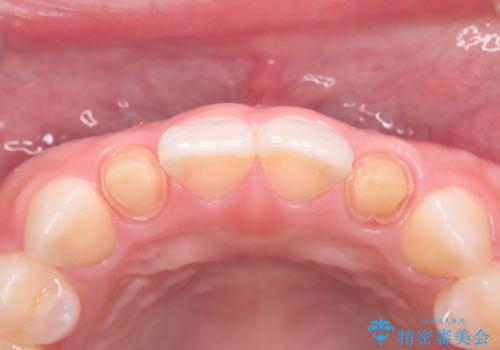

- 食べ物が歯間にはさまることを主訴に来院された患者様です。レントゲンより上顎両側切歯に根管治療が実施されていますが、被せ物が入っておらず、充填物に劣化像もみられました。歯の色の差も気にされていたのでオールセラミッククラウンにて治療いたしました。

より歯の色をきれいに見せたいという希望があったため、ホワイトニングも実施いたしました。食べ物の詰まりも改善し、きれいな仕上がりになったので非常に満足いただけました。